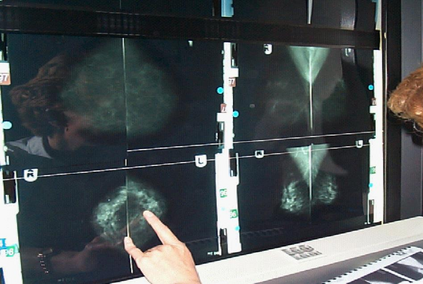

The need for AI systems to provide explanations for their behaviour is now widely recognised as key to their adoption. In this paper, we examine the problem of trustworthy AI and explore what delivering this means in practice, with a focus on healthcare applications. Work in this area typically treats trustworthy AI as a problem of Human-Computer Interaction involving the individual user and an AI system. However, we argue here that this overlooks the important part played by organisational accountability in how people reason about and trust AI in socio-technical settings. To illustrate the importance of organisational accountability, we present findings from ethnographic studies of breast cancer screening and cancer treatment planning in multidisciplinary team meetings to show how participants made themselves accountable both to each other and to the organisations of which they are members. We use these findings to enrich existing understandings of the requirements for trustworthy AI and to outline some candidate solutions to the problems of making AI accountable both to individual users and organisationally. We conclude by outlining the implications of this for future work on the development of trustworthy AI, including ways in which our proposed solutions may be re-used in different application settings.

翻译:现在人们普遍认为,需要AI系统对其行为作出解释,这是其通过的关键。在本文件中,我们研究了值得信赖的AI问题,并探讨了在实践中提供这种服务的实际意义,重点是卫生保健应用。这一领域的工作通常将值得信赖的AI视为涉及个人用户和AI系统的人-计算机互动问题。然而,我们在这里争辩说,这忽略了组织问责制在人们如何理解和信任AI在社会技术环境中所发挥的重要作用。为了说明组织问责制的重要性,我们在多学科小组会议上介绍了乳腺癌筛查和癌症治疗规划的人类学研究的结果,以表明参与者如何对彼此和他们所加入的组织负责。我们利用这些调查结果丰富目前对可信AI要求的理解,并概述一些备选解决办法,以解决使个人用户和组织都对AI负责的问题。我们最后概述了这项工作对未来工作的影响,即制定可靠的AI,包括在不同应用环境中重新使用我们提出的解决办法的方式。